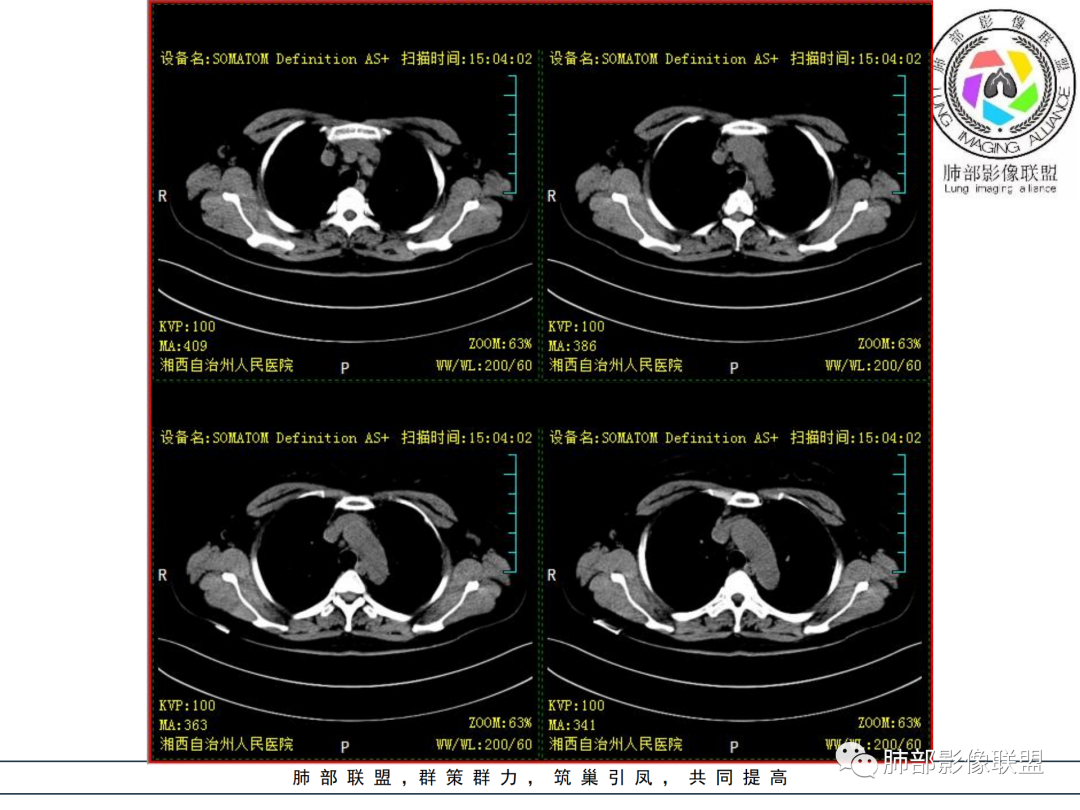

1.中年女性,发现双肺多发病变,且增多增大。

缺乏呼吸道症状及中毒症状,实验室炎性指标不高

既往多关节肿痛一年余,被诊断“类风湿”。此次就医无关节肿痛。

2.双肺多发片状影,胸膜下分布为主,部分沿支气管血管束分布,边界不清,实性及磨玻璃密度,趋于柔和,可见支气管进入或穿行,未见空洞、钙化及树芽等。部分病灶显示反晕。

3.未见腔积液。

4.双肺门及纵隔未见增大淋巴结。